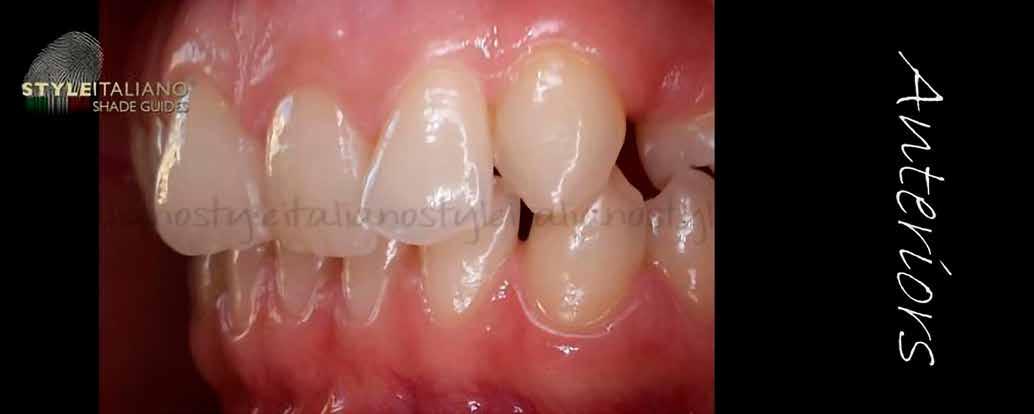

Esetbemutatás

A 19 éves hölgypáciens azzal a kéréssel jelentkezett a rendelőnkbe, hogy szebb fogakat szeretne. Az első konzultáció alkalmával megkérdeztük, hogy mi zavarja leginkább a fogazatának jelenlegi megjelenésében, valamint azt is megbeszéltük vele, hogy milyen végeredmény elérése esetén lenne maradéktalanul elégedett. Ebben az esetben a kezelési célokat az alábbiakban határoztuk meg:

A páciens fogazata esztétikai megjelenésének és funkcionális működésének a lehető legtöbb, saját foganyag megtartása mellett történő helyreállítása (1. és 3. ábra). A lehető legideálisabb esztétikai végeredmény elérése érdekében néhány esetben a fogak alakjának módosítá -

sára is szükség van (2. és 4. ábra).

A kezelés megtervezése során kifejezett jelentősége van annak, hogy jó kommunikáció legyen a páciens, a fogorvos és a fogtechnikus között. A páciens leendő fogazatának természetes megjelenését a kezelésben részt vevő team szakmai felkészültsége, gyakorlati tapasztalata és a kezelés sikerességének irányába történő elkötelezettsége biztosítja. A beavatkozások megkezdése előtt megtörtént a páciens anamnézisének a felvétele, valamint a klinikai kivizsgálását is elvégeztük. Ezt követően lenyomatokat készítettünk a kiindulási állapotról, majd a kiindulási helyzetet extra- és intraorális fotók segítségével is rögzítettük (13. a-c. ábra).